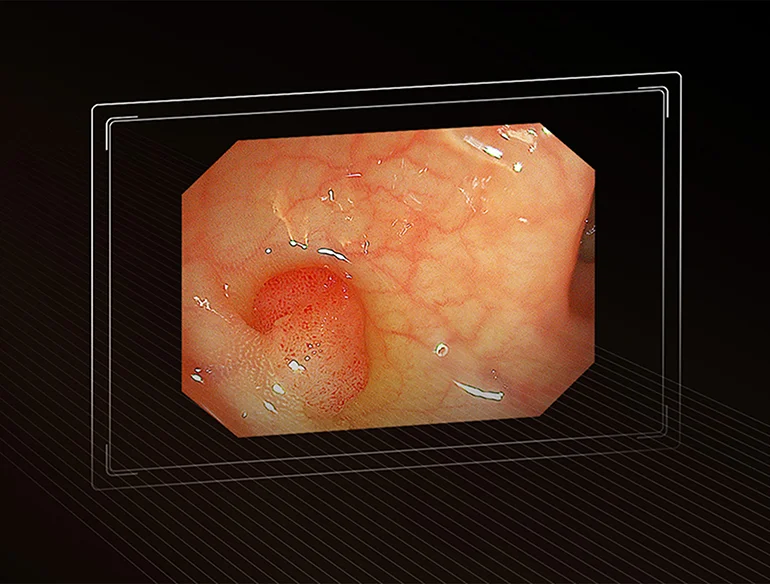

Изображение в формате Full HD

Обеспечивают разрешение Full High Definition (1920*1080P), превосходное качество изображения и более реалистичную цветопередачу. Четкие и ясные клинические изображения помогают рассмотреть мельчайшие детали слизистой оболочки.